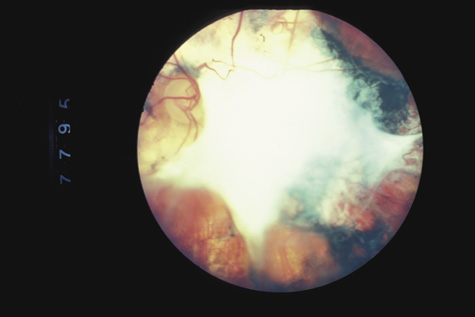

RETINITIS SCLOPETERIA

Retinitis sclopeteria is the rupture of the choroid or retina caused by shock waves generated by passage of a high-velocity missile through the orbit without directly striking the eye. Initially a subretinal or vitreous hemorrhage is seen. If the optic nerve is damaged, visual acuity can be profoundly decreased. In severe cases, massive amounts of fibrous tissue proliferate into the eye (Fig. 27). In others, as the blood clears, a claw-like break is often seen in Bruch's membrane and in the choriocapillaris (Fig. 28). Retinal detachment rarely occurs at the site of the injury, probably because of binding of the retina to the choroid by fibrous tissue, but late detachment from a break at a distal site can occur.97,98

Fig. 27. A: the left eye of a man who shot himself with a pistol. The bullet passed through both orbits, behind the globes. The optic nerve is at the left of the photograph. There is extensive fibrous proliferation. B: The right eye has considerably less retinal damage, but the visual acuity is hand movements because of optic atrophy.

Fig. 28. A: An equator plus photograph shows retinitis sclopeteria. B: Higher power view of the sclopeteria.